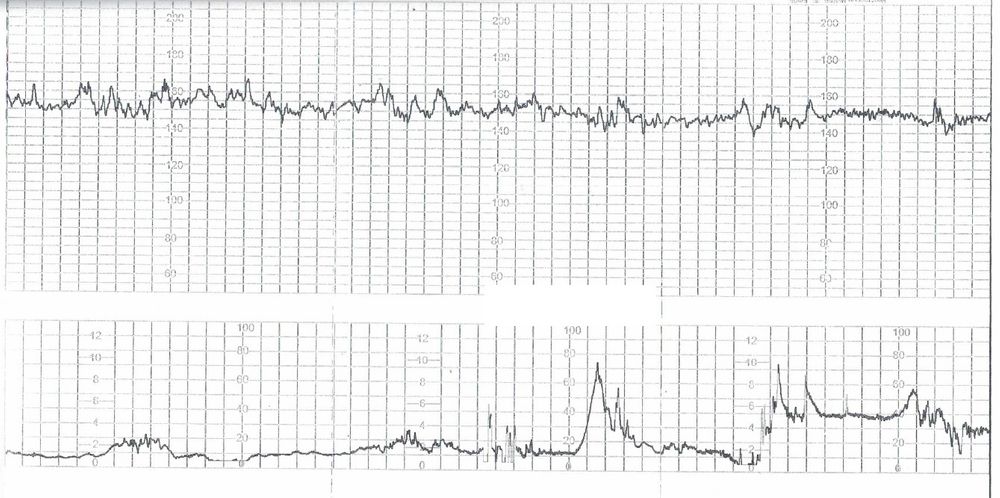

Расшифровать КТГ при родах

Добрый день! Я правильно понимаю, что на второй половине нижнего графика - схватки?

Да, правильно. Но схватки очень короткие и нерегулярные, м.б. у вас только предвестники родов?

Спасибо за ответ! Родовая деятельность в дальнейшем развивалась. Роды были в тот же день.